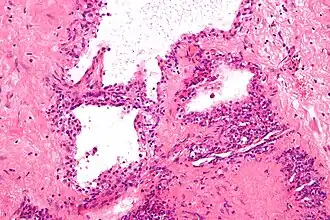

![]() Micrografía mostrando un cistoadenoma seroso de páncreas, un tipo de cistoadenoma. H&E stain | ||